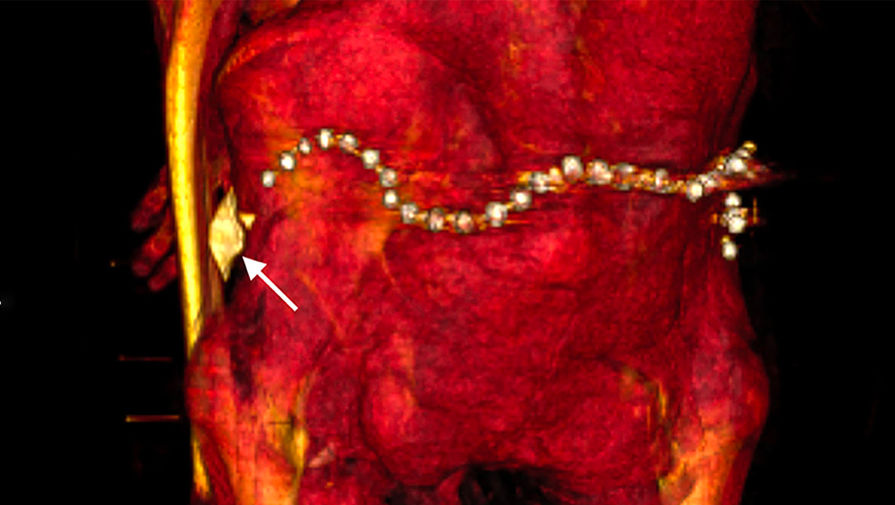

В бинтах исследователи также обнаружили около 30 украшений, в частности пояс из металлических (вероятно, золотых) бусин в задней части тазовой области, и фаянсовый амулет в форме раковины улитки у левого бедра.

Некоторые из украшений, вероятно, появились при повторном захоронении, считает Салим — так бальзамировщики хотели компенсировать ущерб, нанесенный грабителями.